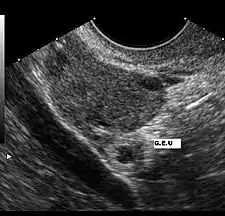

El ultrasonido es probablemente la herramienta más importante en el diagnóstico de un embarazo extrauterino, especialmente si se combina con otros métodos. Con mayor frecuencia, se utiliza para confirmar un embarazo intrauterino.[12] La visualización de un saco intrauterino, con o sin actividad cardíaca fetal, a menudo es suficiente para excluir un embarazo ectópico.[11] La excepción es en el caso de un embarazo heterotópico, la combinación de embarazos intra y extrauterino que, aunque es una situación excepcional, se ven cada vez más frecuentes, entre 1 de 4000 a 1 de cada 30 000 embarazos espontáneos. El estudio de los anexos uterinos por un ultrasonido es obligatorio en pacientes sometidas a estimulación ovárica y la reproducción asistida a pesar de la visualización de un embarazo intrauterino, porque son pacientes que tienen 10 veces mayor riesgo de embarazo heterotópico.

El ultrasonido transvaginal tiene mayor resolución que el abdominal y puede ser usado para visualizar un embarazo intrauterino 24 días después de la ovulación o 38 días después del último período menstrual, que suele ser alrededor de 1 semana antes de los que es posible visualizar un ultrasonido transabdominal. El saco gestacional —un término ecográfico y no anatómico— es la primera estructura que se reconoce en un ultrasonido transvaginal.[11] Se ve en el ultrasonido como una zona ecogénica gruesa en torno a un centro hipogénico correspondiente a la reacción decidual trofoblástica que rodea el saco coriónico. Las estructuras que representan a un embrión en desarrollo aún no se pueden reconocer sino hasta una mayor edad gestacional.[13]